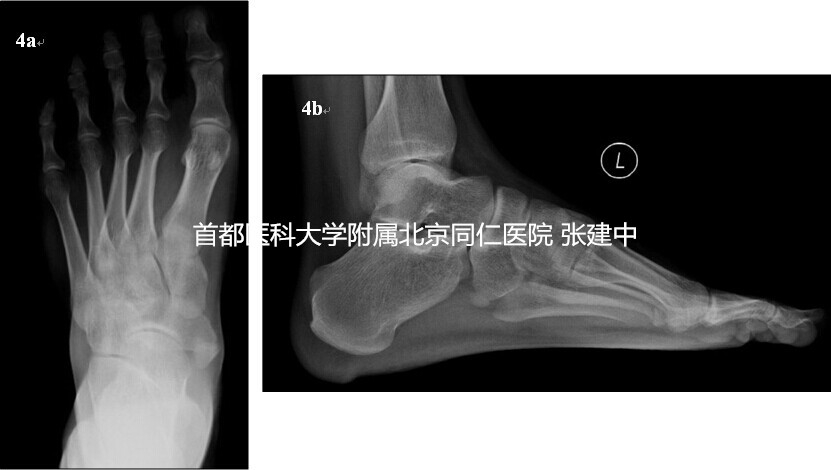

图4. 4a. 患足负重正位X线,示II型副舟骨存在;4b. 患足负重侧位X线,示副舟骨存在及足弓情况

患者,男,27岁,因“左足内侧疼痛2年,加重1年”来诊。患者诉左足内侧疼痛,疼痛与行走及劳累明显相关,休息后缓解。查体:患足足弓正常,无跟骨外翻。足内侧舟骨结节处稍膨隆,为骨性突起,压痛明显。余无异常表现。负重位X线示左足存在副舟骨,为II型(图4a,4b);为进一步明确副舟骨疼痛原因为腱性还是骨性,行SPECT-CT检查,结果回示副舟骨及副舟骨与舟骨关节部位无核素浓聚,提示局部无骨代谢增高(图5)。诊断为II型副舟骨,根据临床查体及SPECT-CT结果判断其症状来源于胫后肌腱止点及周围软组织,而非舟骨与副舟骨之间关节处。据此,手术方案制定为副舟骨切除并胫后肌腱止点重建术。术中在足内侧以舟骨结节为中心做一纵行切口,长约4-5cm,显露舟骨结节及副舟骨,探查见副舟骨上的胫后肌腱止点周围存在损伤与炎性改变。显露副舟骨与舟骨之间的间隙,自该处切除副舟骨,清理并切除部分损伤的胫后肌腱止点处组织,约1cm,以2号不可吸收线编织缝合胫后肌腱远端,保留缝线4-5cm,备用。以骨刀去除舟骨结节跖侧面皮质,以4.5mm直径钻头在舟骨结节自背侧向跖侧钻取骨孔,将胫后肌腱从跖侧向背侧穿出骨孔,折返缝合,达到重建胫后肌腱止点的目的。术后以石膏托将患足固定于跖屈内翻位,6周后去除石膏托,开始主动活动患足。2个月开始部分负重,逐渐过渡到完全负重。